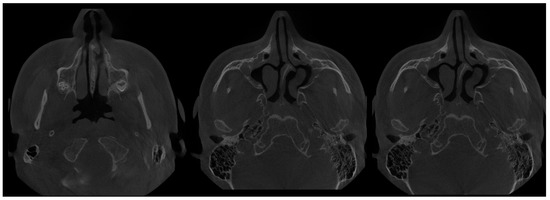

- Type 5 Mixed form SSS-CMA on both MCs (Figure 9)—present asymmetrically, combines both forms of SSS and CMA in pure or in-pure forms;

- Type 7 MSH = maxillary sinus hypoplasia (Figure 10 and Figure 11)—a very rare, probably somehow atypical case of complete symmetrical MS retraction and atrophy, without CRS. Possible relation to bilateral MSH—bilateral maxillary sinus hypoplasia should be considered and requires further studies [33].